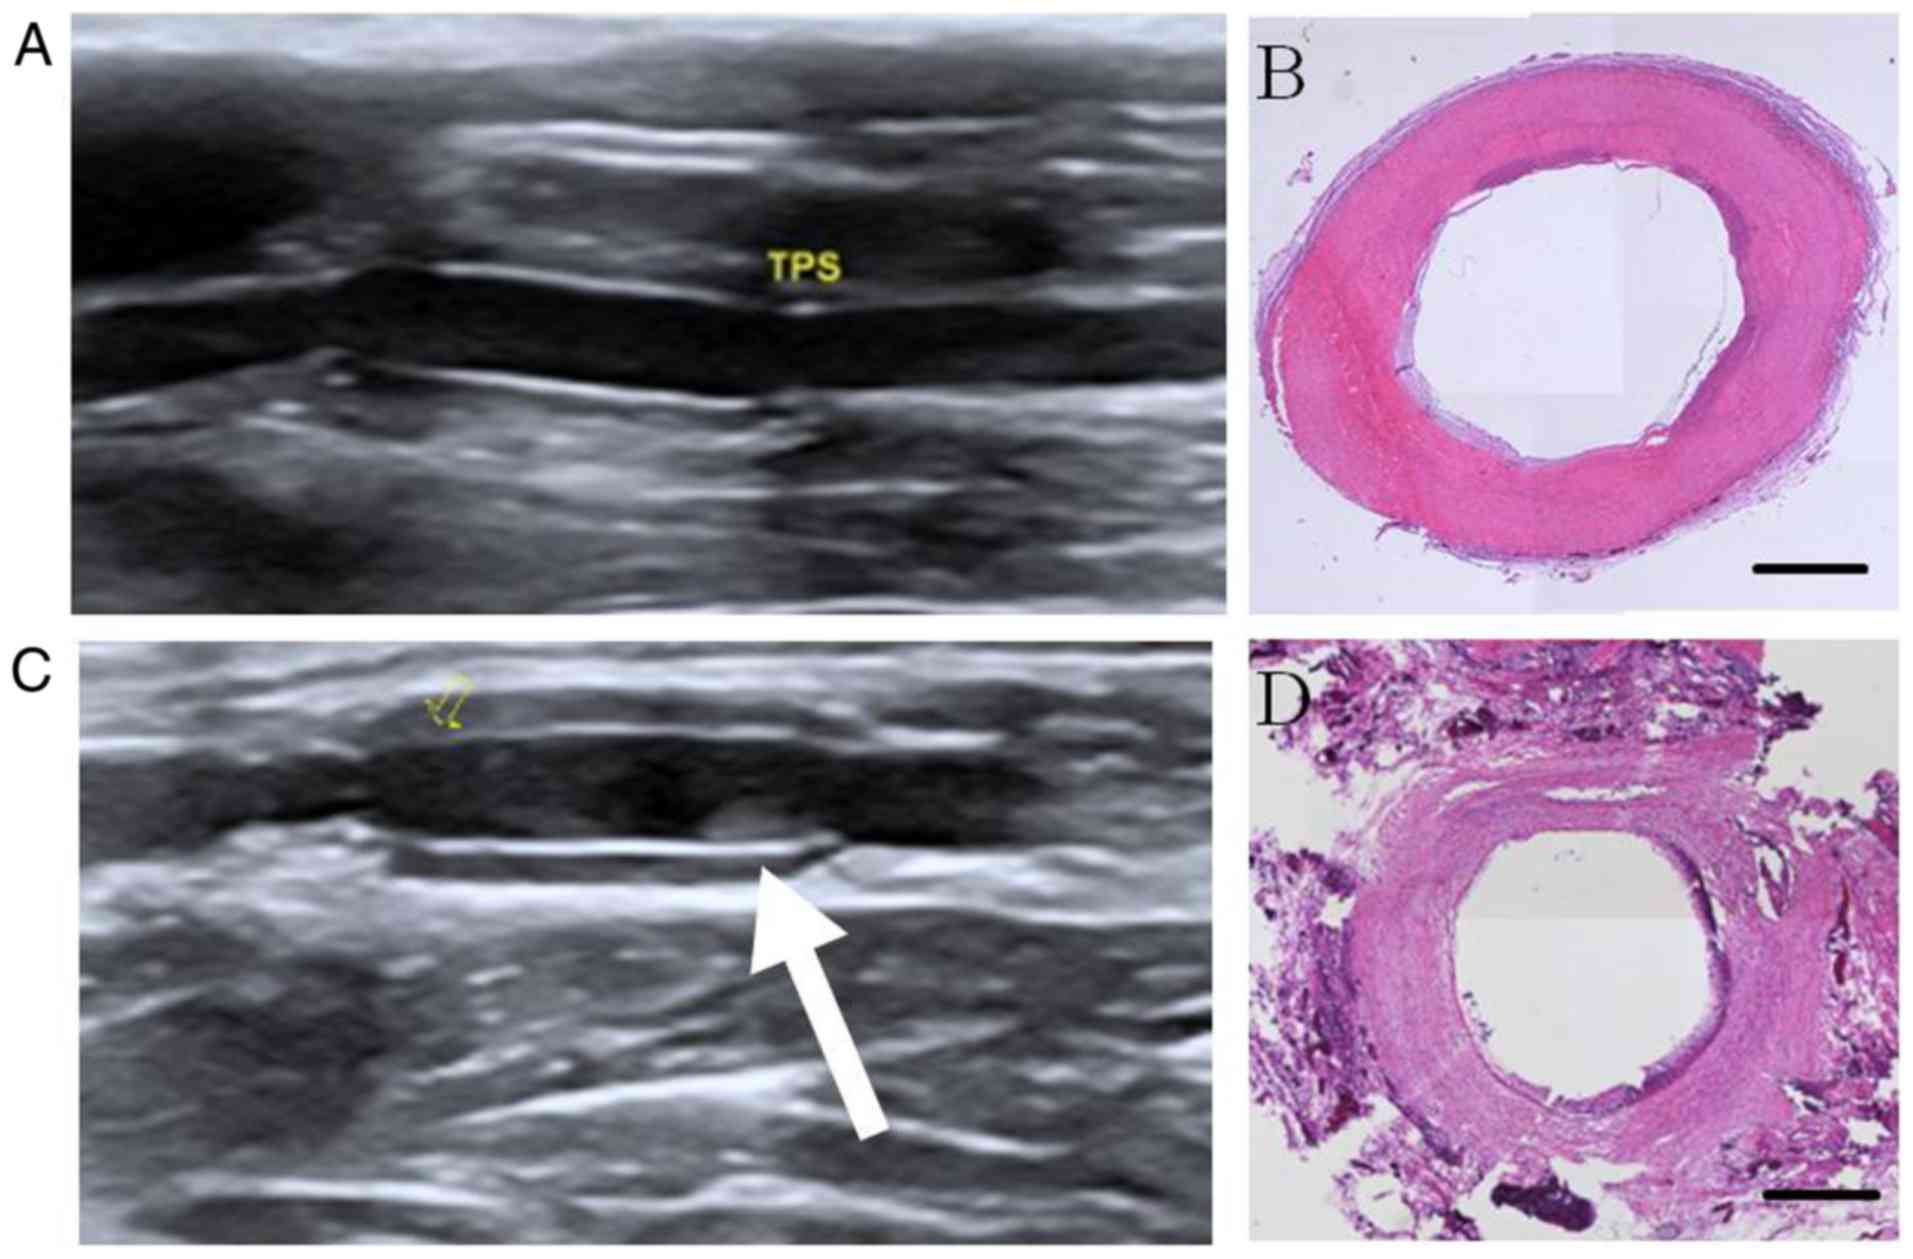

Global tropical cyclone extreme wave height climatology, Accurate and continuous ultrasonography evaluation of small

Accurate and continuous ultrasonography evaluation of smallイーグルピアス頭金 タディアンドキング TADY&KING tady&king